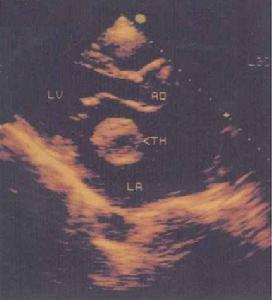

心臟血栓造影本品靜脈給予,50%~80%的病人出現發熱、發冷、寒戰、噁心及嘔吐、頭痛及肌肉與關節痛。本品的急性不良反應為上腹部痛或腹絞痛、腹瀉(有些病人伴有胃腸道出血)、低血壓、焦慮及血栓形成性靜脈炎。兒童比成人為多見。肌注可產生嚴重的局部反應。本品主要危險性是對腎臟的毒性作用,減少劑量也不能避免腎臟損害,並常為永久性的損害。有些病人出現支氣管痙攣及顯著的嗜酸細胞增多,其他的特異性反應為急性肝功能衰竭、潮紅、周身疼痛、心臟停搏及室顫、癲癇大發作、血小板減少及嚴重過敏性血栓形成。在動物或人未見致癌作用。